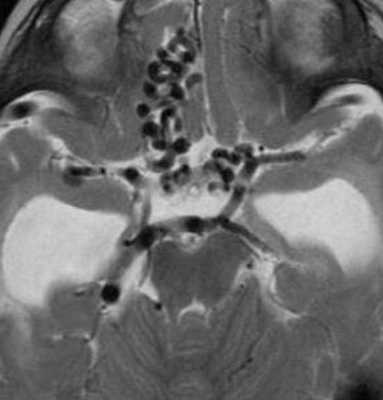

При МРТ головного мозга на аксиальных МРТ любого типа выявляется округлое образование с отсутствием сигнала в области пластины четверохолмия. На сагиттальных МРТ головного мозга отчетливо видно расширение и отсутствин сигнала от расширенной медианной прозэнцефалической вены, а также часто от прямого синуса и синуса намета. При МРА видна расширенная артерия. Тромбированные участки мальформации дают повышенный сигнал на МРТ головного мозга любого типа. На КТ видно скопление контраста в расширенной вене. Ангиография позволяет разделить АВГ на 4 типа в зависимости от питающей артерии.

МРТ головного мозга, Т2-взвешенная аксиальная МРТ. Расширенные ветви ПМА и ЗМА.